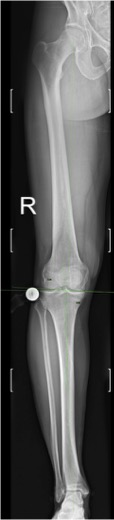

- Die Röntgenaufnahmen unter Belastung zeigen eine Einengung des innenseitigen Gelenkspalts im Sinne der medialen Gonarthrose Stadium III.

Die Ganzbeinaufnahme zeigt eine O-Beinstellung (Varus) mit Verlagerung der Traglinie nach medial

- Die Analyse der Achsen- und Winkelverhältnisse des Beines ist integraler Bestandteil unserer Beratung und kann nur an einer Ganzbeinaufnahme . Hier zeigt sich als wesentlicher Befund eine Varusbiegung der Tibia (Schienbein), welche die O-Beinstellung begründet.

LDFA 89°

MPTA 84° !!!

JLCA 2°

MAD 25 mm